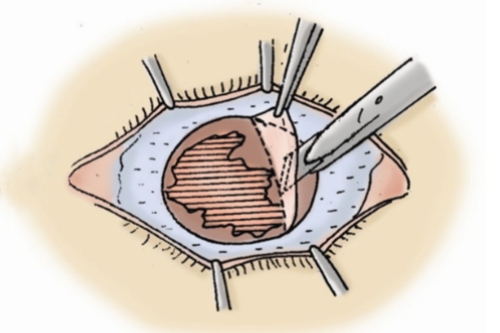

技术亮点:保留健康内皮层,排斥率≤5%,1个月即可拆线

适用人群:全层混浊或穿孔(如化学伤、溃疡)

含金量:飞秒激光辅助切口(精度0.1mm),术后散光降低40%

黑科技:3mm微切口植入,无需缝合,术后次日可视物,适合大泡性角膜病变

飞秒激光移植系统实现微米级切割,供体利用率提升40%